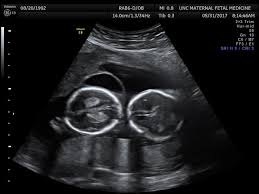

Development Twins In The Womb Week By Week, Multiple Pregnancy And Birth Twins Triplets And High Order Multiples Booklet : Fraternal twins in the womb:. These deviations are one of the reasons why a singleton fetal weight chart shouldn't be applied to twins. The bladders, brains, livers, kidneys, reproductive organs, spines, legs and arms already start to develop. By the third week of pregnancy, each fertilized egg forms into a ball of hundreds of cells and becomes known as a blastocyst. 5,9 mm fetal heart rate: Find out whether or not twins can be detected in week 5.

These deviations are one of the reasons why a singleton fetal weight chart shouldn't be applied to twins. 6 weeks pregnant with twins Each twin at 20 weeks is about 26cm (10.2in) long, though it's still common for one twin to be bigger than the other. Identical twins occur when a single fertilized egg splits and develops into two fetuses. Fraternal twins in the womb:

There's also a lot going on inside your babies' heads too. Fraternal twins in the womb: By next week, this cavity will envelop the embryo and continue to house your baby throughout your pregnancy. The normal declaration of growth in twins can seem like an issue, even if it isn't. Twins in the womb the average gestational age for twins at birth is 36 weeks. Your babies' bodies are now in proportion to their heads. Ladies pregnant with twins might experience more significant levels of nausea in their beginning trimester. And see the whole nine months in one timeline!

Genetically, the two babies are identical. It's starting to get a little cramped as the uterus expands to accommodate your growing babies. Fraternal twins in the womb: Your babies are shedding most of their downy body hair as well as some of the vernix caseosa, the creamy substance that protects the skin. Identical twins occur when a single fertilized egg splits and develops into two fetuses. This week i realized that i have been having heartburn. By the time you're four weeks pregnant, your twins will each be about the size of a poppy seed. Your babies' fingernails and toenails have now grown in. Your babies' bodies are now in proportion to their heads. Ensuring the babies continue to be healthy and your own body is in its best shape to handle the situations of the coming months is necessary. Their lungs are well developed by 34 weeks. Weight, still too small to measure. Others have only peach fuzz.

20 mm fetal heart rate: Twin pregnancy week by week: With your uterus pushing up near your diaphragm and putting pressure on your abdomen, you may be dealing with heartburn more often or feeling a. They are temporary and usually are gone by the 32nd week of pregnancy. By the time you're four weeks pregnant, your twins will each be about the size of a poppy seed. Find out whether or not twins can be detected in week 5. They'll swallow all this and turn it into a blackish mixture called meconium that will come out in their first bowel movement. The fetal brain may create these cysts as a normal part of development.

Fraternal twins in the womb: From conception, twins are formed when one of two events happen. What this means is that each twin forms from an individual fertilized egg. The normal declaration of growth in twins can seem like an issue, even if it isn't. Weeks 1 to 7 and the week by week twin pregnancy development during this period the babies weigh less than one ounce. You may test positive if you take a pregnancy test at this point. Ohhh great !!!you are pregnant.congratulation!!feta development week by weekweek 4 to week 40week 4: It concluded that dichorionic twins deviates from singleton reference charts at approximately 32 weeks. 164 bpm, the other one is 33,7 x 18,4 fetal length: Ensuring the babies continue to be healthy and your own body is in its best shape to handle the situations of the coming months is necessary. With your uterus pushing up near your diaphragm and putting pressure on your abdomen, you may be dealing with heartburn more often or feeling a. Your babies are shedding most of their downy body hair as well as some of the vernix caseosa, the creamy substance that protects the skin. It's starting to get a little cramped as the uterus expands to accommodate your growing babies.

Twins in the womb the average gestational age for twins at birth is 36 weeks.